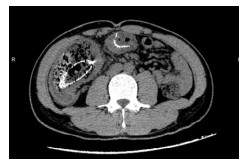

病例3,患者男,33岁。2019年7月6日因“上腹部胀痛10余天”来院急诊,拟“肠梗阻”收治入院。入院查体:腹膨隆,上腹部正中压痛,无反跳痛。CT提示:①横结肠局部肠壁增厚伴管腔狭窄,近段肠管梗阻扩张(图 4);②右肝后段低密度影,建议MR增强。肝脏MR增强:①横结肠局部肠壁明显增厚伴强化,考虑横结肠癌;②肝内多发小斑点,转移瘤可能。肠镜检查示:横结肠肿物,取病理活检后,行肠镜下横结肠支架置入术。肠镜病理提示:横结肠印戒细胞癌。3 d后复查腹部平扫CT示原先扩张的肠腔已明显缩小(图 5)。经多学科讨论后认为目前患者急性肠梗阻症状已明显缓解,建议转肿瘤内科先行转化治疗。患者分别于2019年7月19日、8月7日和8月29日共行三次FOLFIRI方案化疗。2019年9月20日复查腹部增强CT示:横结肠癌支架术后,较前相比,局部肠壁增厚明显减轻;右肝低强化结节灶较前缩小。于2019年9月23日转入普外科,术前再次行多学科讨论后,于10月4日行腹腔镜下横结肠癌切除手术(图 6),手术过程顺利。术后病理报告:横结肠印戒细胞癌,T3N1M1。患者术后接受定期规律辅助化疗,目前恢复良好。

| 图 4 腹部增强CT示横结肠、升结肠及近段小肠肠管梗阻扩张明显 |